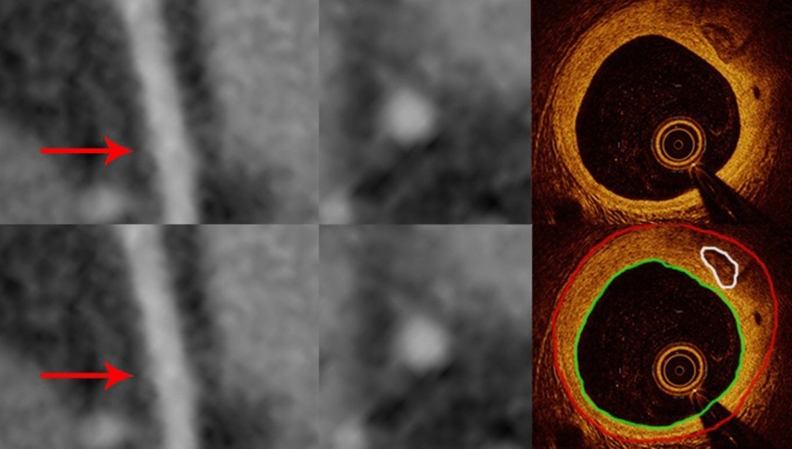

Among 87 calcified plaques visualized by OCT, 74 (85%) were identified by CCTA (Fig. 2) and 12 were not identified due to small plaque size (≤ 0.25 mm2) (Fig. 3). The sensitivity, specificity, positive and negative predictive values, and accuracy for detecting calcified plaque by CCTA were 87%, 100%, 100%, 87% and 89% respectively.

Figure 3.

Curved multiplanar reformation computed tomographic images (left) and the cross-sectional (middle) views of the left anterior descending coronary artery from CCTA (red arrows) do not show coronary calcification seen on the corresponding OCT image (right) where a small calcified plaque of 0.25 mm2 is present. The red contours encompass the vessel wall and the green ones outline the vessel lumen.